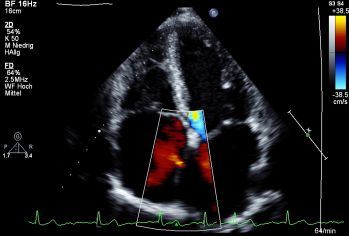

Eine Echokardiographie ist heutzutage eine Routineuntersuchung, die bei allen Erkrankungen des Herzens oder dem Verdacht darauf durchgeführt wird. Ohne Strahlenbelastung lassen sich hier zum Beispiel Herzklappenfehler, Fehlbildungen oder Bewegungsstörungen des Herzens darstellen oder auch Informationen über die Pumpleistung des Herzens gewinnen.

- Farbdoppler-Echokardiographie: Herzultraschall zur Erkennung von Klappeninsuffizienzen und -stenosen